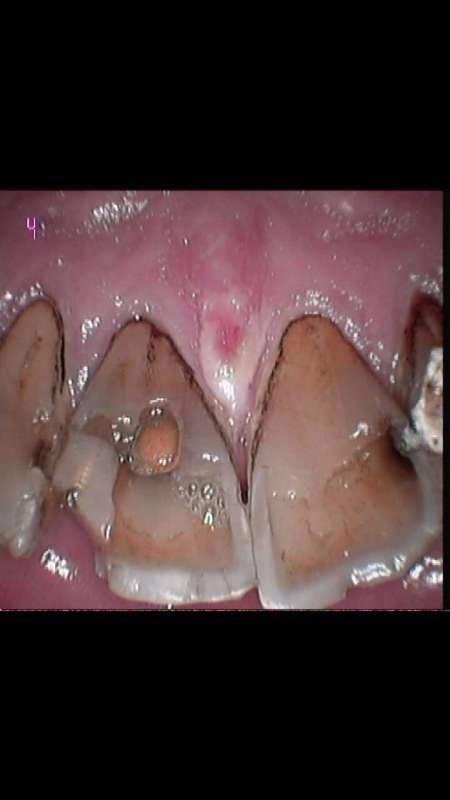

前门牙烤瓷修复

前门牙根管治疗3年后,牙齿变色,要求全瓷修复